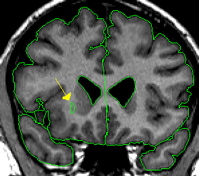

|  | The putamen is a subdivision of the lenticular nucleus (the other division is the pallidum). The lenticular nucleus from the axial view resembles a rounded triangle that is divided into two major sections. The putamen is the lateral part of this triangle.The putamen starts small and ends small in the coronal view. The putamen quickly grows to its greatest size in the middle and in the medial posterior portion it closely resembles a goldfish shape. The putamen lies lateral and partially anterior to the thalamus. It is bordered laterally, superiorly, and inferiorly by white matter. The putamen is usually bordered medially by the pallidum. When the pallidum is not yet present or has already disappeared the putamen is bordered medially by the internal capsule. | |

It is important not to include the claustrum in the putamen; this is the strip of tissue bordering the lateral edge of the putamen. Often the putamen can be extracted at the same time as the caudate especially in the area where they are connected by the nucleus accumbens. The histogram of the caudate, in many cases, is close to what you want for the putamen as well. After extracting the caudate, before deleting the remaining red lines, you can often go immediately into the intensity contour function and adjust them to fit the putamen.  This should be done separately for each hemisphere. | ||

| Part II - Blood vessels There is often a blood vessel near the inferior border of the putamen, this should not be included as part of putamen. The vessel should be extracted separately using a contour line and labeled "vessel." The vessel will serve as at least a portion of the inferior border. | ||